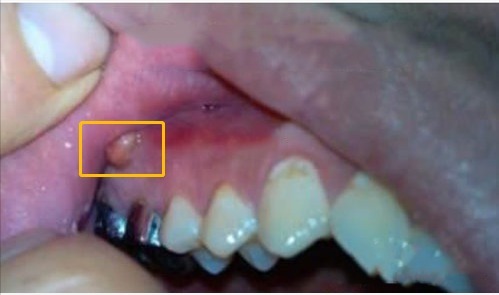

什么是牙龈癌牙龈癌,顾名思义,是发生在牙龈的恶性肿瘤,多为高分化的鳞状细胞癌,以溃疡型最为多见。下牙龈较上牙龈多发,肿瘤生长缓慢,男性多于女性。牙龈癌的病因目前还不是十分明确,但长期慢性刺激是一个重要因素,如喜欢吃过热或辛辣食物、大量吸烟喝酒、残留在口腔内的残根残冠、不合适的假牙等慢性刺激。牙龈癌早期可能会被误以为是口腔溃疡、牙周炎、牙周病等,没有引起足够的重视,等到肿瘤发展起来的时候,肿瘤可能已经转移到淋巴、颅内、胸腔等地方,对身体造成很大危害。所以,早期发现很重要!

牙龈癌有什么症状早期症状有点出血或者牙龈部位有点不舒服,伸舌头的时候会发现这个地方好像有个东西突起。很多人都觉得这个东西不影响进食,就没有去管它。当肿瘤进一步发展时,会出现牙龈区破溃疼痛出血,可以看到菜花样肿物,有口气异味,大部分患者在这时才感觉不对劲,去医院就诊。晚期的时候,肿瘤会扩散到牙槽,侵犯牙槽骨和牙齿,使牙槽骨松动,导致牙齿脱落或移位,这是肿瘤可转移到其他组织。当病情在进一步发展时,会出现张口困难、不能咀嚼等情况,影响患者进食。